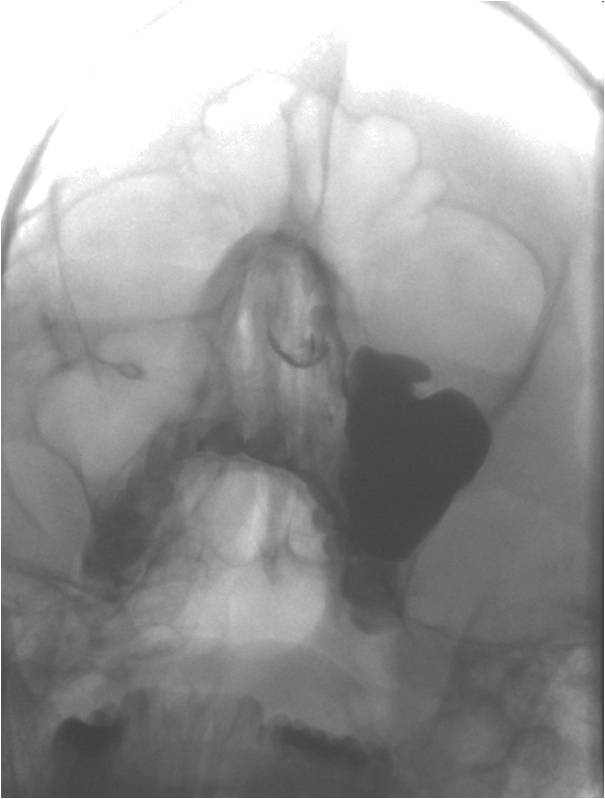

Пример двойной локализации кист правой гайморовой полости - верхне-наружная и передне-базальная...